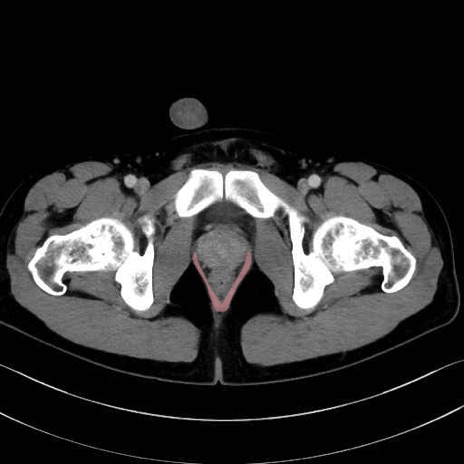

肛門挙筋(levator ani muscle)のCT画像の解剖

肛門挙筋 (Levator ani)